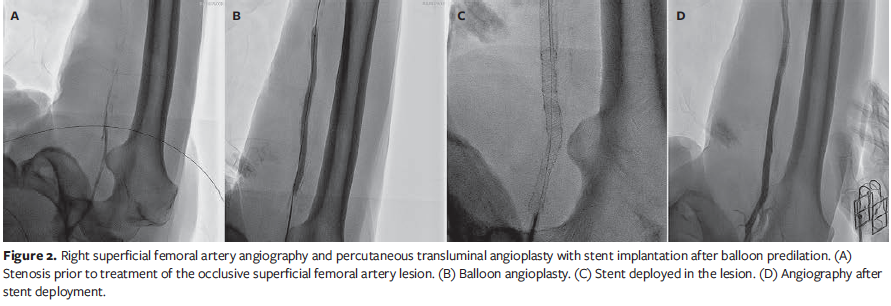

On postoperative day 6, a sudden drop in the right ABI to 0.36 was observed, accompanied by dampened monophasic waveforms on Doppler images. Emergency PTA was performed, during which the cardiologist (B.L.) placed 2 Supera self-expanding interwoven nitinol stents (Abbott Vascular), measuring 5.5 mm × 150 mm and 6.5 mm × 150 mm, within the occlusive lesions of the right SFA. Imaging studies performed immediately after this procedure revealed good vascular patency within the previously occlusive lesions (Figure 2).